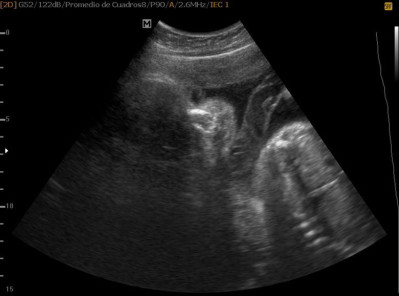

Varias ultrasonografías en 2D y 3D

Envíado por Dr. Nelson Menjívar Sarco